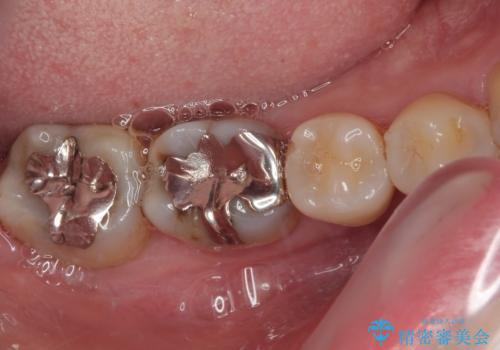

- 当院で矯正後に銀歯が目立つのでやり替えたいと来院された患者様です。銀色の詰め物(メタルインレー)と歯の間に隙間を認め、あまり歯を削りたくないとのことで患者様と相談の結果右下の7番目の歯はセラミックインレー、右下の6番目の歯はメタルインレーが大きいためフルジルコニアクラウンでの治療を行うことになりました。